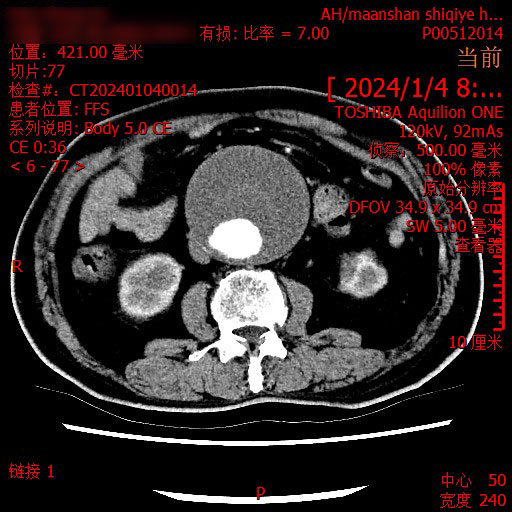

正当一家人走投无路之际,在朋友的介绍下,2024年1月,患者来到了马鞍山十七冶医院肿瘤精准诊疗中心,刘永彪主任携团队亲自为他量身定制了治疗方案,考虑到腹主动脉夹层,同时召集医院感染科、老年病科、心血管内科、肿瘤科等专家进行会诊。经过一系列的检查,明确病情,直肠中分化腺癌,虽然有手术指征,但伴有腹主动脉巨大瘤,手术风险极高,综合考虑建议先进行放射治疗,患者家属听到可以治疗如释重负,喜极而泣。

2024年1月,患者开始精准定位,进入肿瘤内科进行放射治疗,过程中,主任和他的团队每日至少查房两次,以便观察患者的病情变化,及时调整放疗计量,减少并发症给患者带来的痛苦。因为腹主动脉瘤的高危性,整个治疗过程中,医护人员操作轻柔,治疗仔细,减少副反应给患者腹部带来的刺激。没想到经过第一阶段的放射治疗后,患者的病情便得到有效缓解,便秘、腹泻等症状逐渐减轻。“简直就是奇迹!真没想到放射治疗效果就那么好,这让压在我们心口的石头终于落了地,十七冶医院肿瘤精准诊疗中心的专家医术高明,医德高尚,是咱马鞍山老百姓的福气。”患者家属夸赞道。